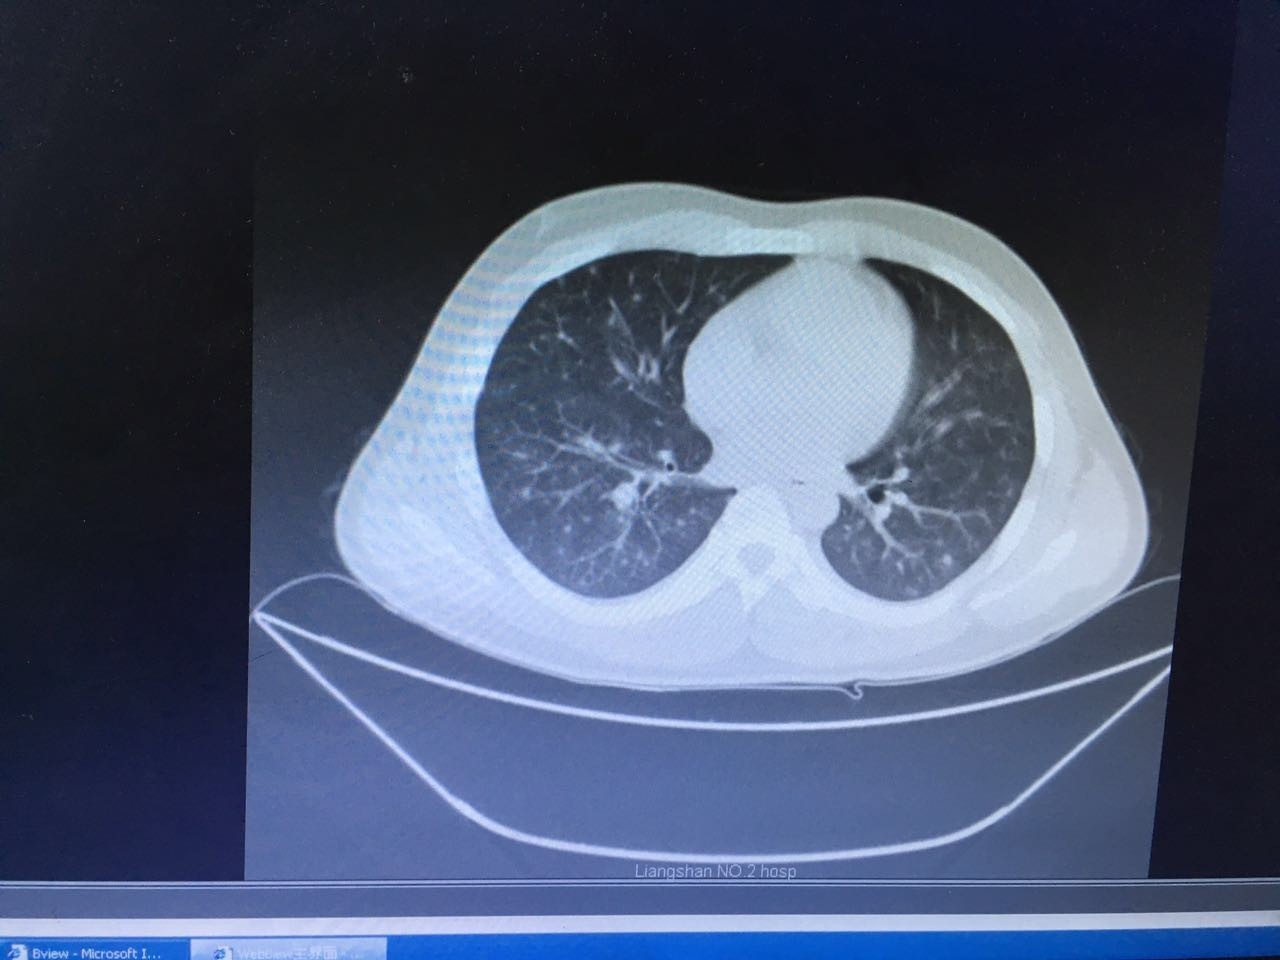

第二天,肺部CT做下来,我们傻了,和胸片差别太大了!从中下肺开始,那是大片的阴影啊!CT提示为间质性肺炎,找放射科主任读片,认为不符合肺结核、肺癌的表现(图1-3.)马上再回到病床前再次确认——没有吸烟史、没有慢性咳嗽史、没有咯血、没有盗汗史。再查体:浅表淋巴结确实不肿大,双肺呼吸音可以算略粗糙也可以算清晰。——这么这么静默的肺部体征,这么这么差的影像学结果,马上补查肿瘤标志物和自身免疫全套吧!

图2